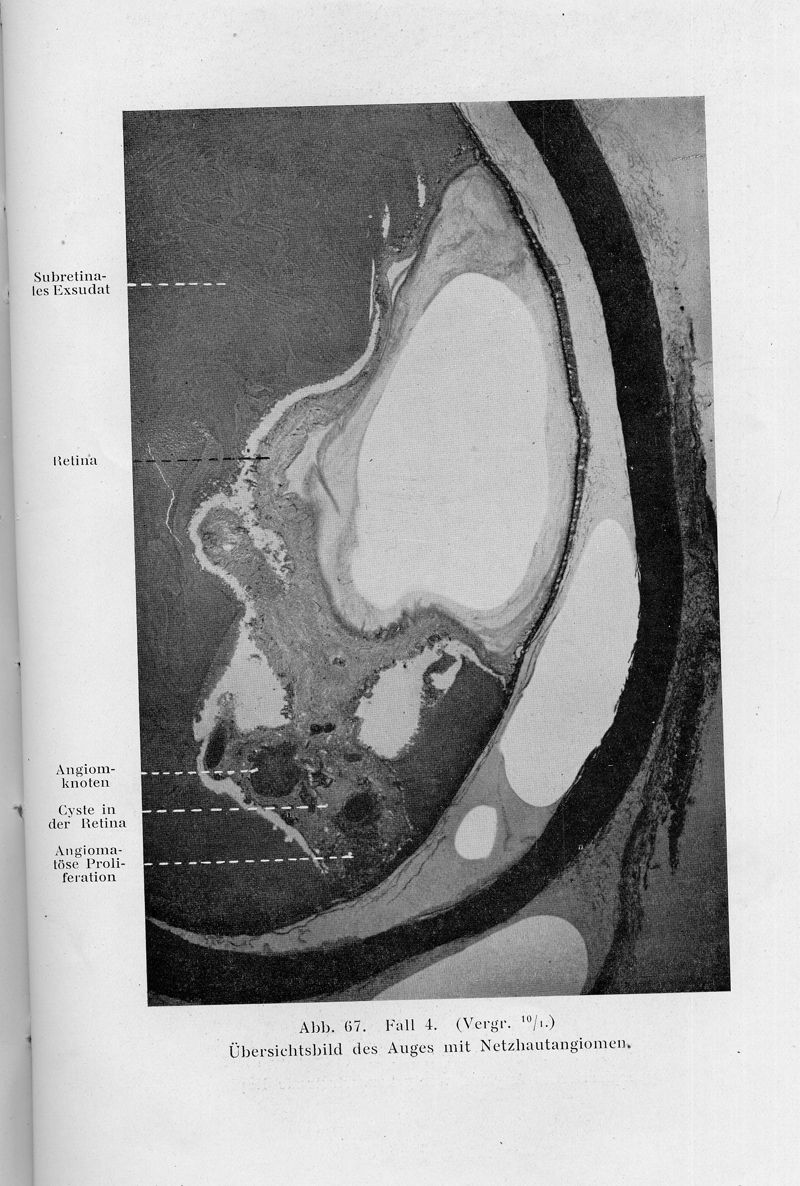

LINDAU, A.

In : Acta Pathologica et Microbiologica Scandinavica, Supplementum,

1926, Vol. 3, suppl. pp. 1-128